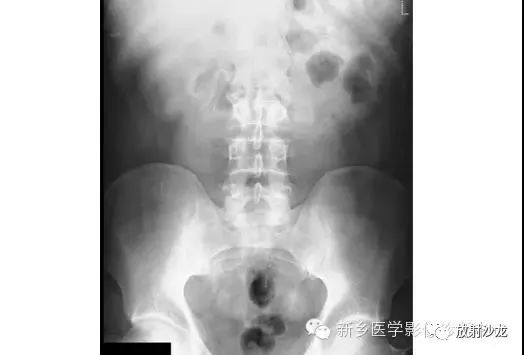

病例四:

急性腹痛、便血的65岁男子行腹部平片检查所上图示。除了近端小肠梗阻,箭头指向有没有其它重大异常?

箭头指向缺血性结肠炎患者的拇指纹。拇指纹是粘膜水肿的非特异性的表现,其可见于炎性肠病、伪膜性结肠炎或缺血性肠病。随着水肿加重,结肠袋可能完全消失,留下一个管状的外观。肠道的收缩狭窄可能是其它常见的发现。